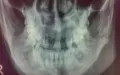

Мне наложили шины, осколочный перелом нижней челюсти без смещений, не могу сказать точного местоположения, т.к. не читал записи в карте (на тот момент было не до того), но в области коренных зубов.

Боли могут быть связаны именно с переломом, а также с неправильным наложением шины. Если нет доверия, необходимо обратиться в ЧЛХ. К сожалению, мне добавить Вам нечего, я не вижу исходной ситуации, а также состояния после шинирования.